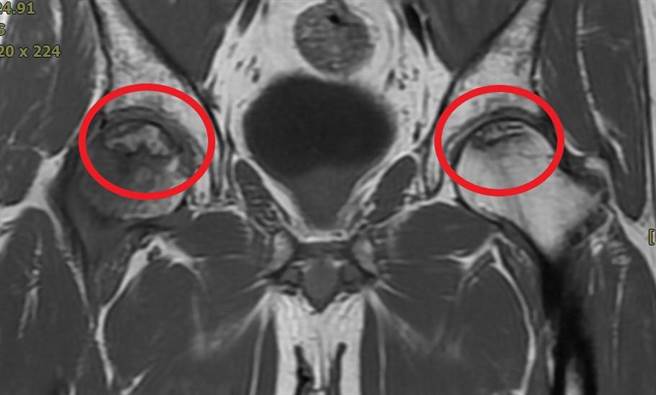

金门1名40岁的业务人员,因工作需要,因此长期品尝金门特产高粱酒,没想到年初时出现走路臀部及髋部酸痛,某个姿势髋关节还会卡住及跛行的症状,于是跨海求助活力得中山脊椎外科医院,经院长杨椒乔诊断,发现男子「双侧髋关节股骨头缺血性坏死」。杨椒乔建议男子利用水介质震波治疗,改善局部血流供应,延缓骨坏死速度,并缓解酸痛。

男子长期喝高粱酒,日积月累下来竟默默形成疾病,男子在今年年初时发现走路臀部及髋部酸痛,某个姿势髋关节还会卡住及跛行的症状,对于行动造成相当大的困扰,于是跨海求助活力得中山脊椎外科医院,才发现是「双侧髋关节股骨头缺血性坏死」。

杨椒乔表示,若对于症状置之不理,身体负重会让股骨头塌陷情形逐渐严重,因此症状会逐渐严重,无法长距离行走,对穿鞋子或蹲下等日常动作感到困难,甚至疼痛到无法行走,且已无法靠药物或减少活动来缓解症状。

杨椒乔说明,当坏死的股骨头塌陷造成关节面破坏时,一般以执行人工关节置换手术为主,但对年轻人来说却是不得已为之的选择。因人工关节使用年限大约为20年左右,未来势必须再次面对人工关节重置手术,而再次手术对周边组织将破坏更甚。此外,术后活动能量也需调整,已不能与术前活动量相提并论,因此建议男子使用水介质震波治疗。